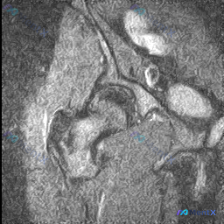

本次分析基于单张髋关节MRI冠状位图像,临床核心问题是:询问影像中是否存在软组织积液。

- 序列与解剖定位:这是冠状位成像,序列推断为T2加权/质子加权,带有脂肪抑制,适合观察水肿和液体病变;图像清晰显示了股骨头、髋臼、股骨颈等核心髋关节结构。

- 系统性阅片结果:

- 骨骼:股骨头形态圆滑无塌陷,股骨颈、髋臼骨皮质连续,无明显骨折线,骨髓信号均匀,未见明显水肿或坏死信号

- 关节结构:关节间隙宽度正常,盂唇形态基本完整,无明显大裂隙或关联囊肿

- 软组织:外侧大转子区域及上方软组织未见肿块或严重水肿,股骨头颈交界区及关节间隙周围未见明显异常高信号积液征象

- 图像局限:部分区域噪声较重,可能影响微小细节判断

基于当前这一单层面图像,未发现明确的异常软组织积液或其他器质性病变,整体影像表现倾向于正常。